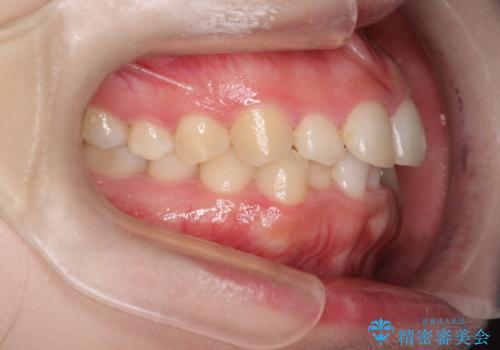

インビザラインでの前歯のガタガタの矯正

- 上下の前歯のがたつきを主訴に来院されました。

歯と歯の間をわずかに削りスペースを作り、インビザラインにて矯正治療を行うこととしました。

使用時間を守っていただけたので、スムーズに矯正を終了することができました。